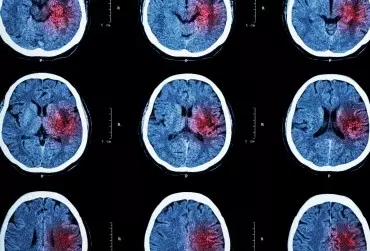

Niedokrwienny udar mózgu u dzieci

Udarem niedokrwiennym mózgu według definicji Światowej Organizacji Zdrowia (WHO) określa się zespół kliniczny cechujący się nagłym wystąpieniem ogniskowych lub uogólnionych zaburzeń czynności mózgu utrzymujących się dłużej niż 24 godziny i niemających innej przyczyny niż naczyniowa. Jeżeli nagłe, ogniskowe objawy neurologiczne z zakresu unaczynienia przez określoną tętnicę trwają krócej niż 24 godziny, definiowane są jako przemijający atak niedokrwienny (transient ischemic attack – TIA).